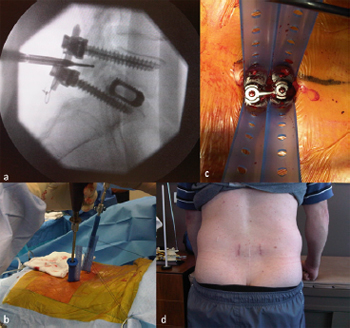

5.2.1. Illustrative patient 2

A 17-year-old male presented with a T12 American Spinal

Injury Association–A spinal cord injury following a high velocity motorcycle accident. Stabilisation surgery was performed the day

of presentation with mobilisation and wheelchair rehabilitation

within 24 hours (Fig. 11). Surgical time was 2 hours, 5 minutes

with 80 mL of blood loss. The patient requested pedicle screw removal

12 months following surgery due to discomfort of the pedicle

screw tulips against his wheelchair.

Fig. 11. Illustrative patient 2, a 17-year-old male who presented with a T12

American Spinal Injury Association (ASIA) – A spinal cord injury following a high

velocity motorcycle accident. (a) Sagittal T2-weighted MRI showing T12 spinal

injury with ASIA – A neurological deficit; (b) intra-operative photograph showing

percutaneous pedicle screw fixation; (c) anterior/posterior image intensifier (II)

radiograph and (d) lateral II radiograph showing stabilisation; and (e) postoperative

photograph showing early mobility within 24 hours.